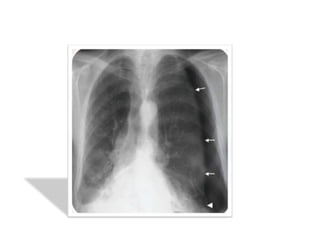

1. LA RX STANDARD DU THORAX

• Elle comporte des clichés thoraciques de face

et de profil en inspiration profonde comme de

pratique courante

• On peut aussi demander des rx de thorax de

face en expiration forcée ( devant des

épanchements minimes )

Apports :

• Affirmer le PNO

• Estimer la taille de l’épanchement

• discuter l’indication d’un drainage(CI si présence

de bulle d’emphysème )

• Analyser le parenchyme pulmonaire sous jacent

et du côté opposé

• Suivre l’évolution retour ou non du poumon à la

paroi

Résultats :

• hyperclarté avasculaire homogène périphérique

prenant tout l’hémithorax plus ou moins étendue.

• Rétraction du poumon s/f d’un moignon hyperdense

sur le hile avec distension des EIC et une netteté

anormale des côtes.

• La plèvre viscérale qui entoure ce moignon apparaît

sous forme d’un fin liséré opaque net comme tracé au

crayon

on recherchera systématiquement les signes

radiologiques associés :

• Une opacité liquidienne à niveau horizontal de la base

témoignant d’un hydropneumothorax

• Position du médiastin et du cœur éventuellement

refoulé

• Anomalies parenchymateuses homo ou contolatérales

en sachant qu’il existe une surcharge vasculaire réflexe

du coté sain

• Un aspect de petit cœur dans les formes bilatérales

• Décollement partiel avec angle de

raccordement aigu à la paroi ou présence de

brides sous forme de bande opaque

• On a une hyperclarté homogène périphérique

en croissant dépourvue de trame pulmonaire

• Si l’épanchement gazeux est minime on peut

avoir une fine bande claire et un « trapping »

cad une zone d’air du décollement qui ne se

vide pas à l’expiration forcée

• Bride rattachant le poumon à la paroi(risque

de rupture et d’hémothorax)